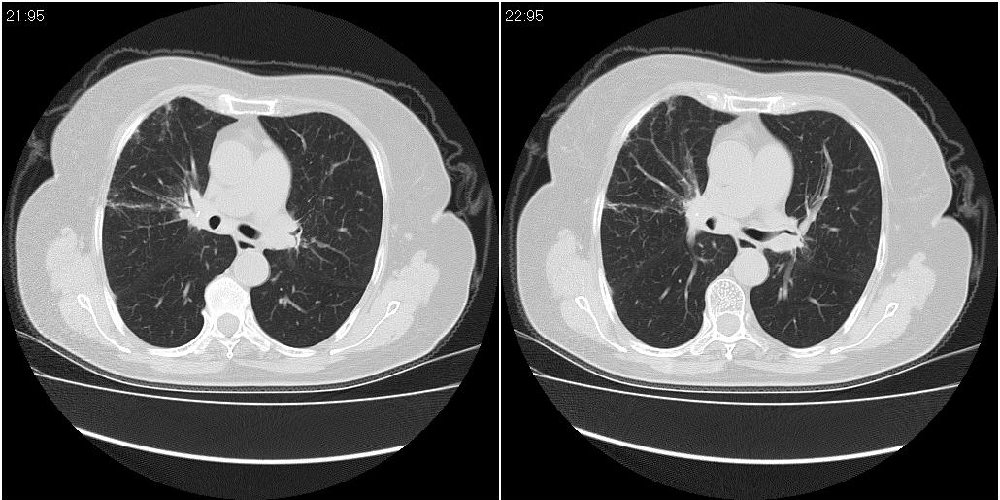

女性,72岁。去年9月份发现肺部病变,诊为肺结核并进行正规治疗至今,但复查后发现ct表现几乎没有变化。

右侧中叶支气管明显狭窄,建议行纤支镜检查!

右中间段支气管局限性狭窄,右中叶支气管亦稍显狭窄,但并未见明显占位表现,半年多了,无变化也许是好事,可能为炎性狭窄,建议继续随访。

双肺继发型tb并右中叶内膜tb,轻度支扩,左下胸膜肥厚粘连。

右中叶炎性改变,支气管狭窄但较光滑,占位可能性不大。

双肺继发性肺结核并右肺中叶节段性肺不张,左下胸膜肥厚粘连。

右肺中叶节段性肺不张,考虑结核或慢性炎症,建议做纤支镜检查。